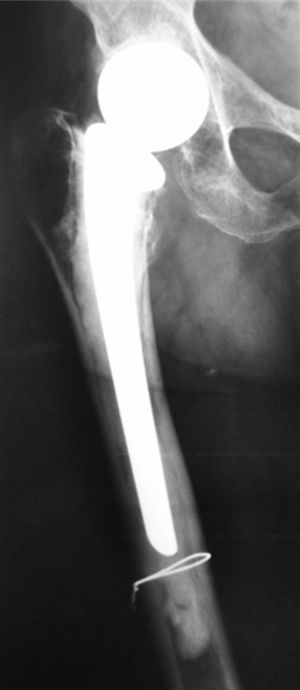

Presentamos el caso de una mujer de 83 años con antecedentes de osteoporosis, posmenopáusica en tratamiento semanal con bifosfonatos y aporte diario de calcio y vitamina D y fractura de cadera derecha a los 64 años, intervenida con colocación de prótesis cementada. Acudió a consulta por coxalgia derecha mecánica, con claudicación en la marcha de meses de evolución. En la exploración destacaron limitación y dolor a la rotación de la cadera derecha. Se realizó una radiografía de cadera (fig. 1) y, ante la sospecha de movilización aséptica de la prótesis, se realizó una gammagrafía ósea en 3 fases que muestra captación en el tercio distal (fig. 2a), confirmando así el diagnóstico. Iniciamos tratamiento con ranelato de estroncio más aporte de calcio y vitamina D. Transcurridos 2 meses, la paciente mejoró significativamente y desapareció la claudicación para la marcha que presentaba con anterioridad. A los 6 meses se repitió la gammagrafía ósea, que mostró una reducción cercana a la normalidad de la hipercaptación isotópica que mostraba al inicio (fig. 2b).